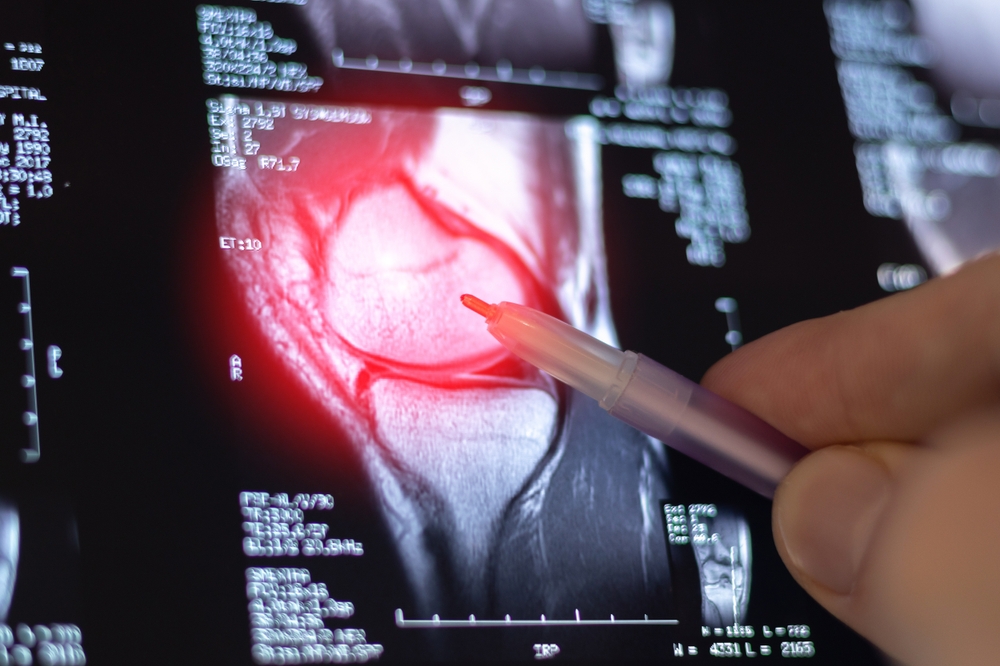

Це не нова проблема — дослідження, опубліковане понад два десятиліття тому, не виявило додаткової користі від артроскопії коліна у людей з остеоартритом коліна порівняно з плацебо-хірургією. Проблема також не обмежується остеоартритом; є докази сильного ефекту плацебо при численних хронічних захворюваннях опорно-рухового апарату, включаючи «тенісний лікоть», біль у плечі, розриви меніска та біль у попереку.

Наприклад, у дослідженні FIDELITY 2013 року порівнювали артроскопічну часткову меніскектомію з псевдотерапевтичною операцією з приводу дегенеративного розриву меніска. У ньому як інтервенційна, так і контрольна групи повідомили про покращення приблизно на 21-23 бали за шкалою Lysholm коліна (міра болю та функції) порівняно з початковим рівнем близько 60 балів, що значно перевищувало мінімальне клінічно важливе покращення в 11,5 балів. Але суттєвої різниці між двома групами в тому, наскільки вони отримали користь, не було.